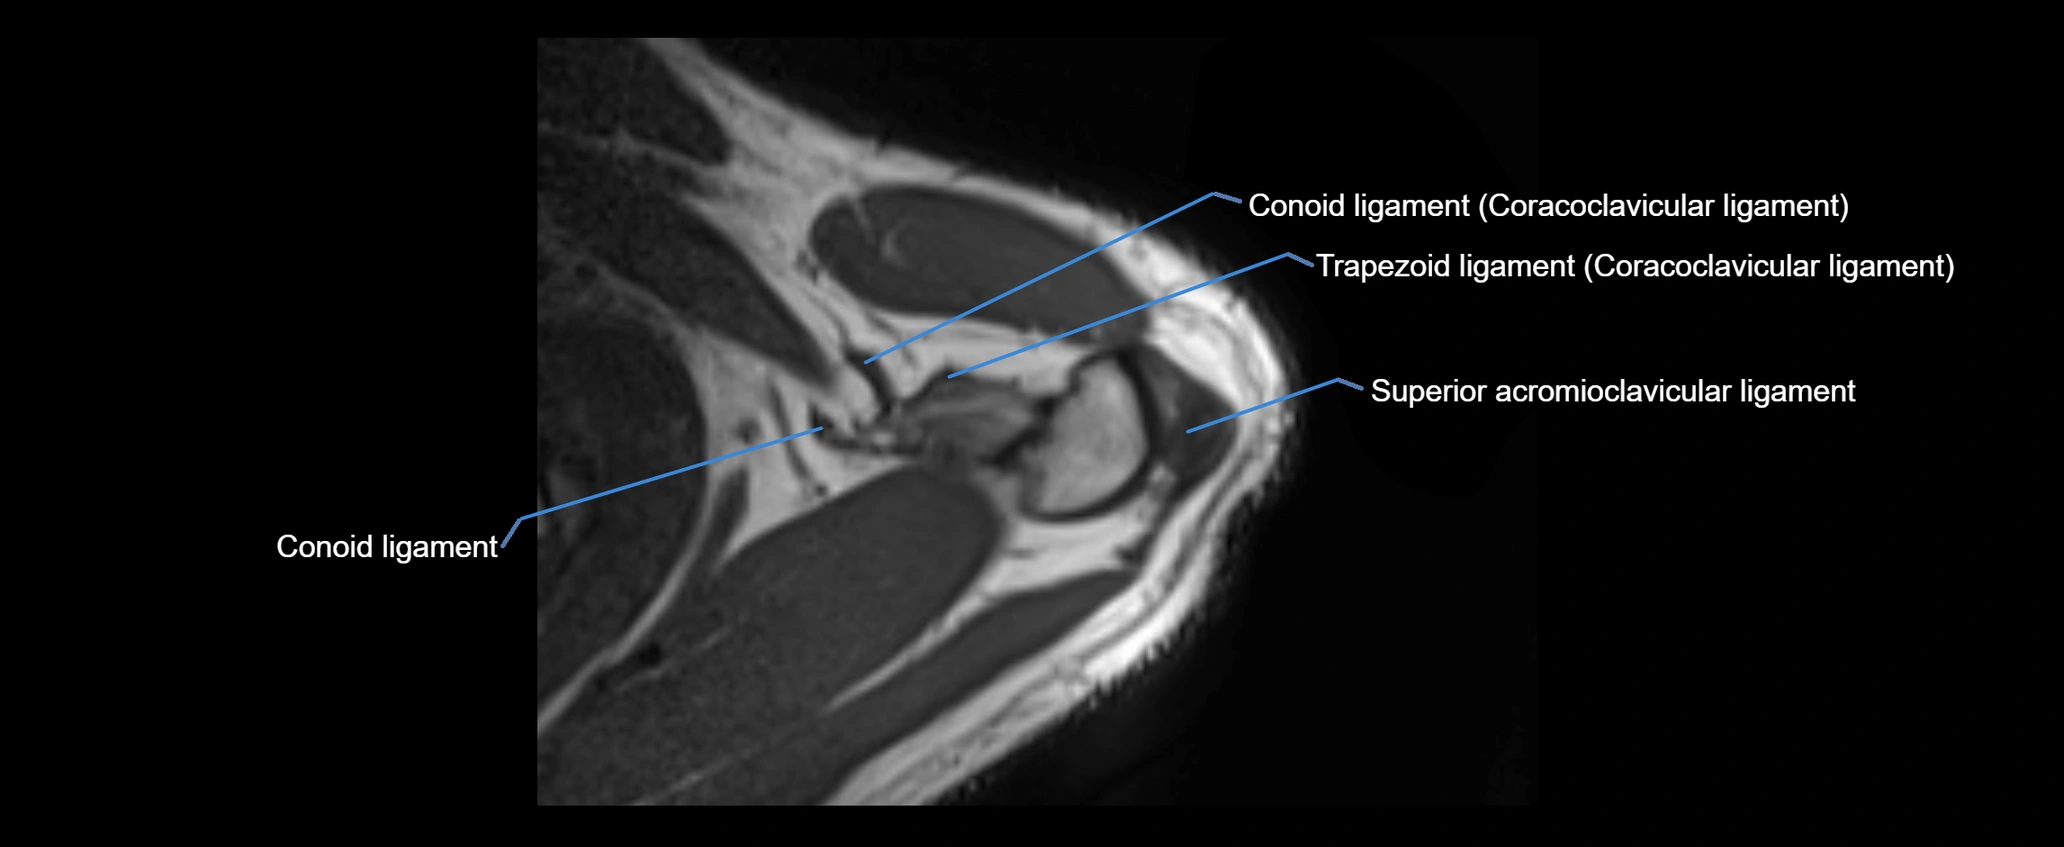

MRI images

image